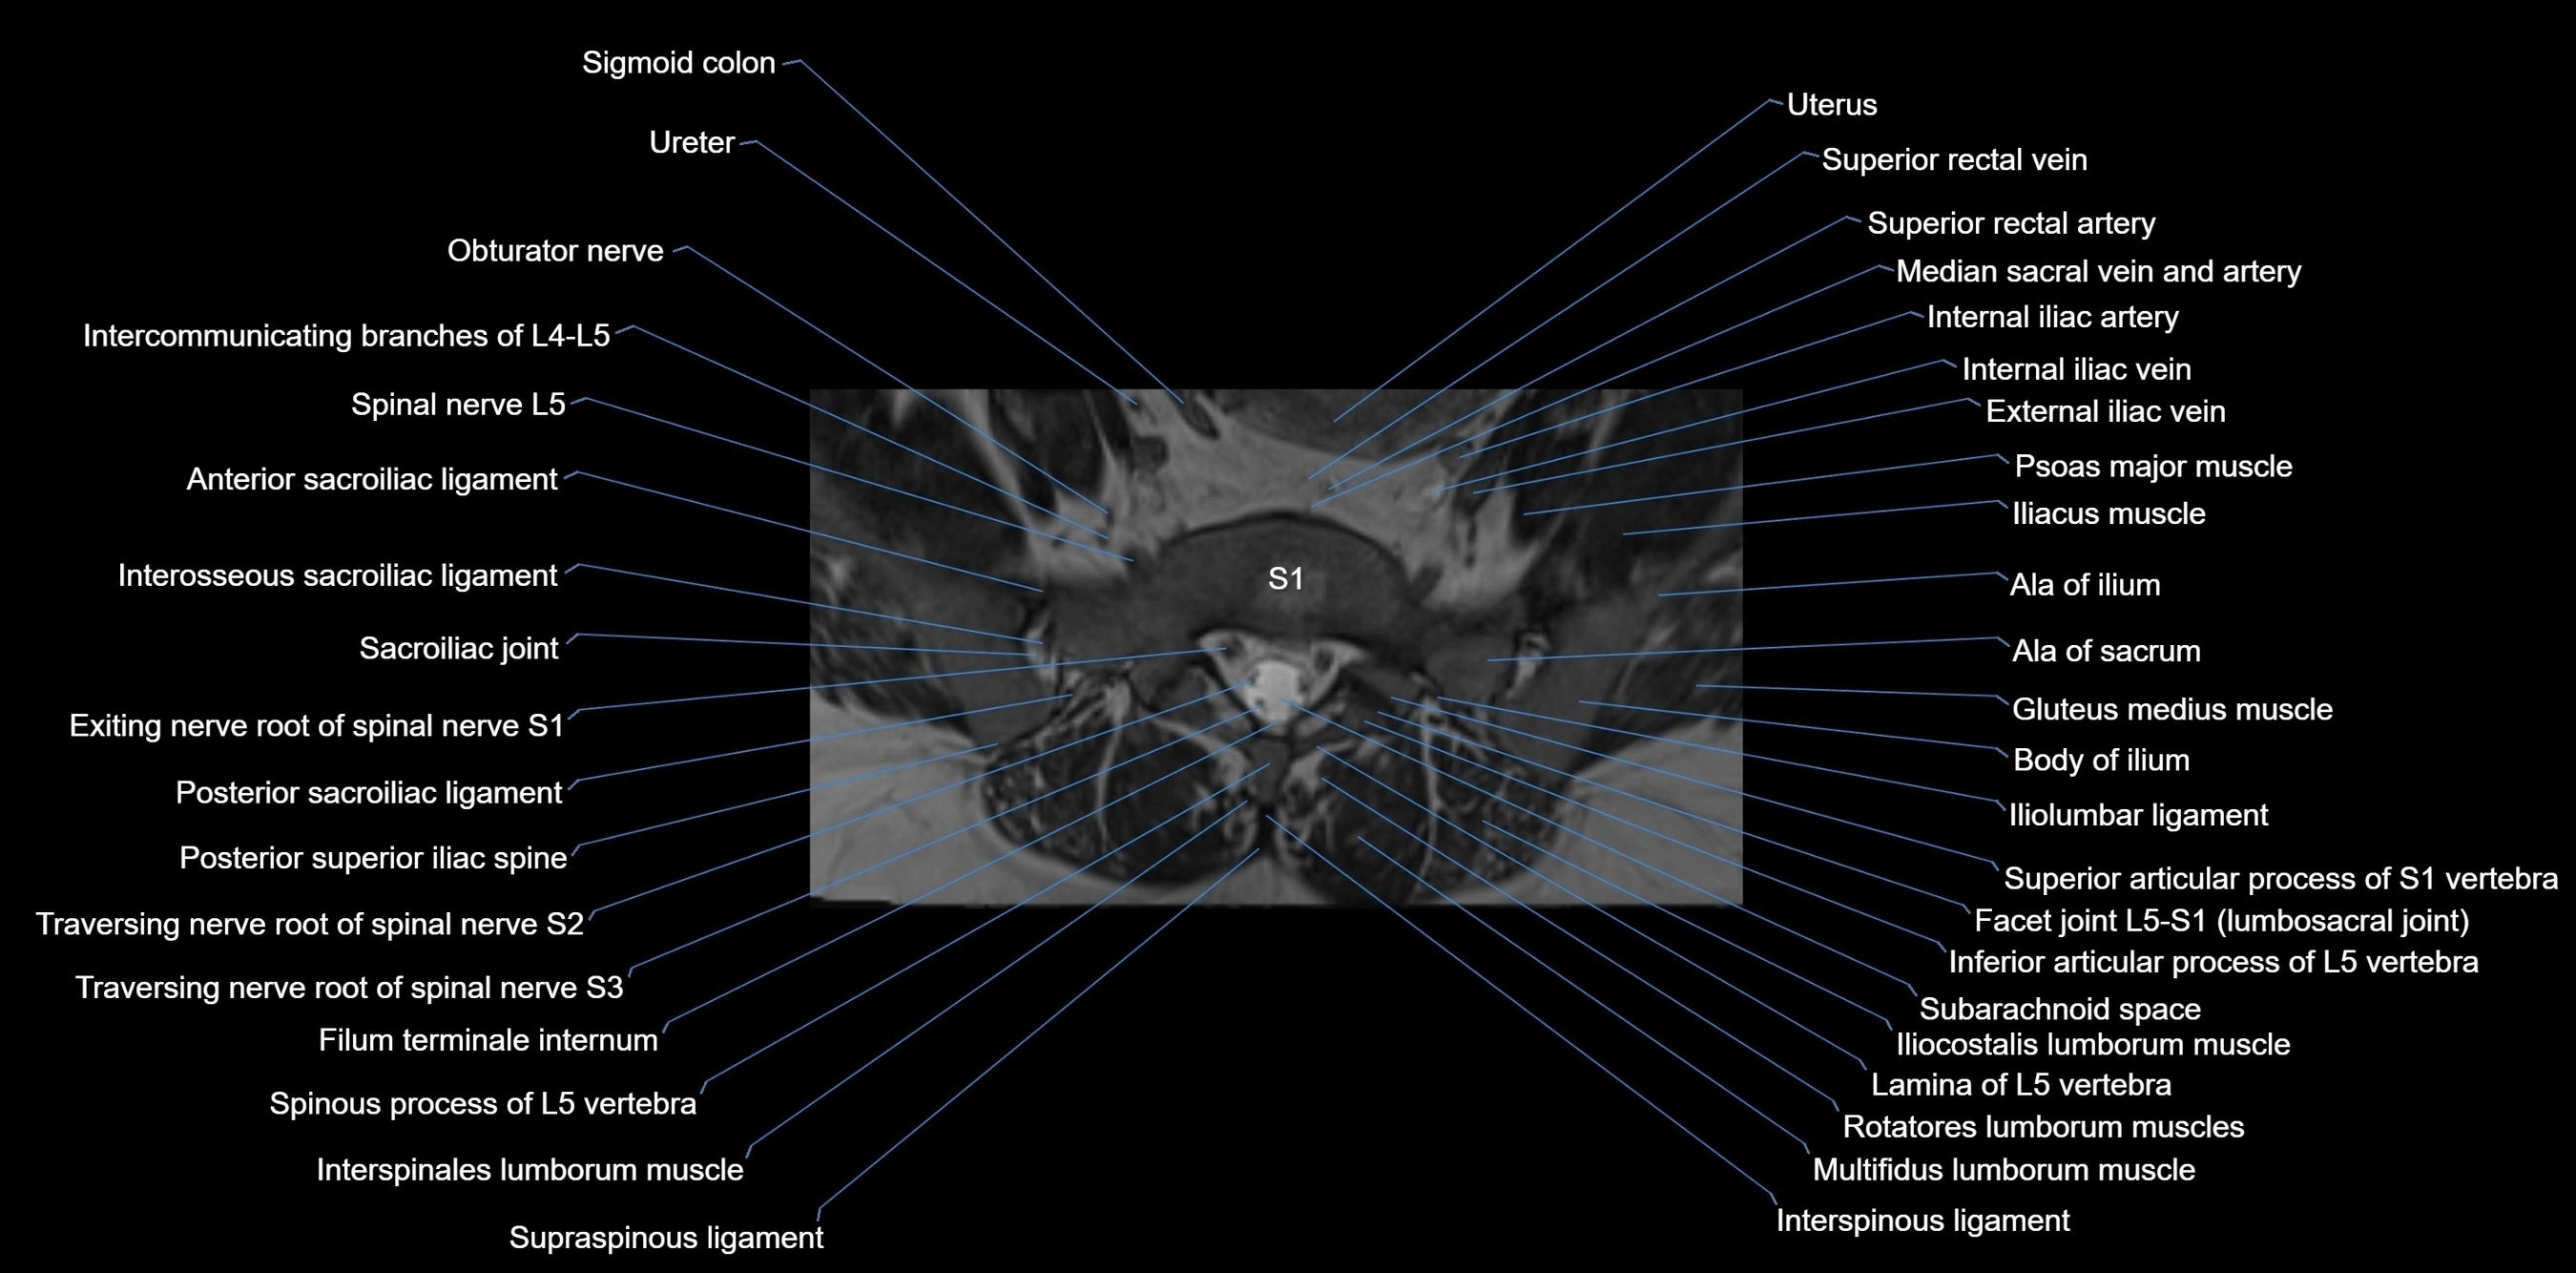

MRI image

image